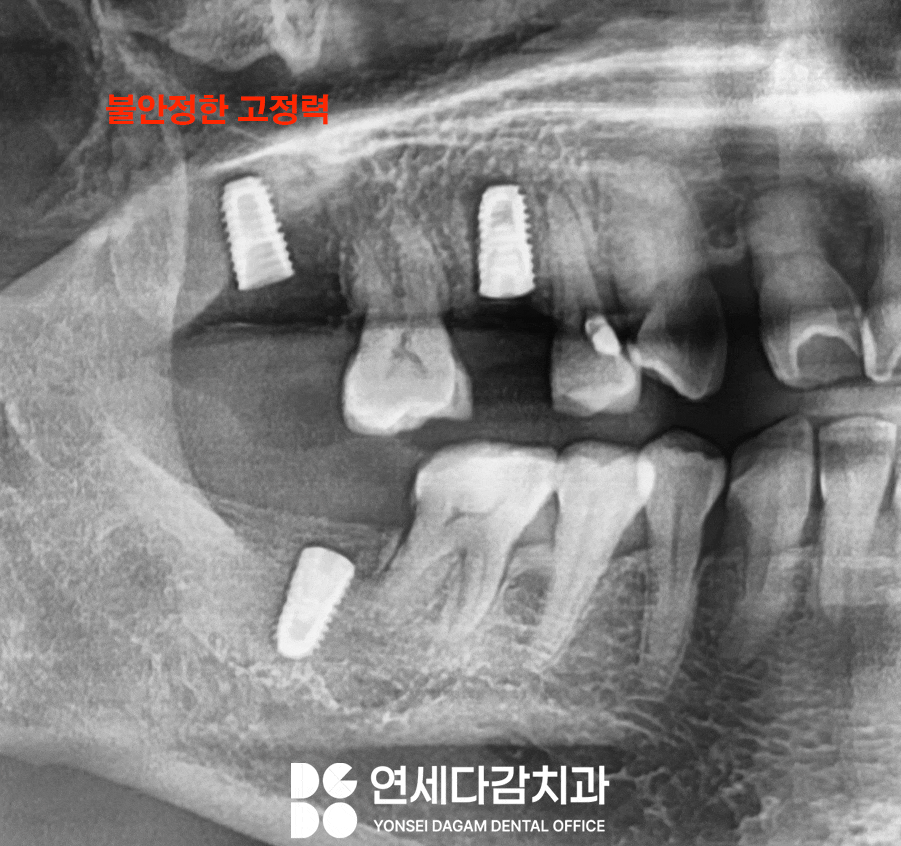

전해 들은 히스토리에 따르면,

해당 부위는 골의 밀도가 낮아서

초기 고정력을 얻기가

어려웠다고 했습니다.